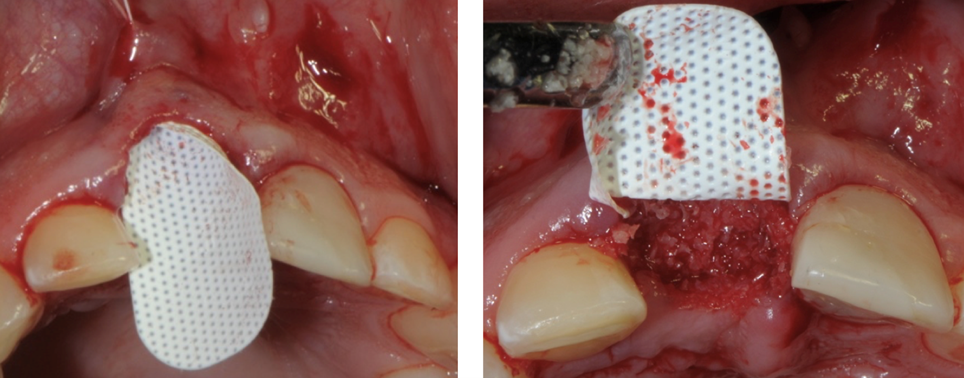

Inserimento della membrana in dPTFE Cytoplast TXT 1224 tramite sutura e posizionamento di sostituto osso suino ad alta porosità Zcore™.

La membrana Cytoplast in d-PTFE viene ritagliata per estendersi di 3-4 mm oltre i margini della cavità e quindi con un curette infilata sotto il periostio del lembo palatale, vestibolare e la papilla interdentale.

La membrana viene ulteriormente stabilizzata usando una sutura incrociata in PTFE Cytoplast®. In alternativa si possono posizionare dei punti interrotti. Le suture in PTFE, che causano una risposta infiammatoria minima, vengono lasciate in sito per 10-14 giorni.